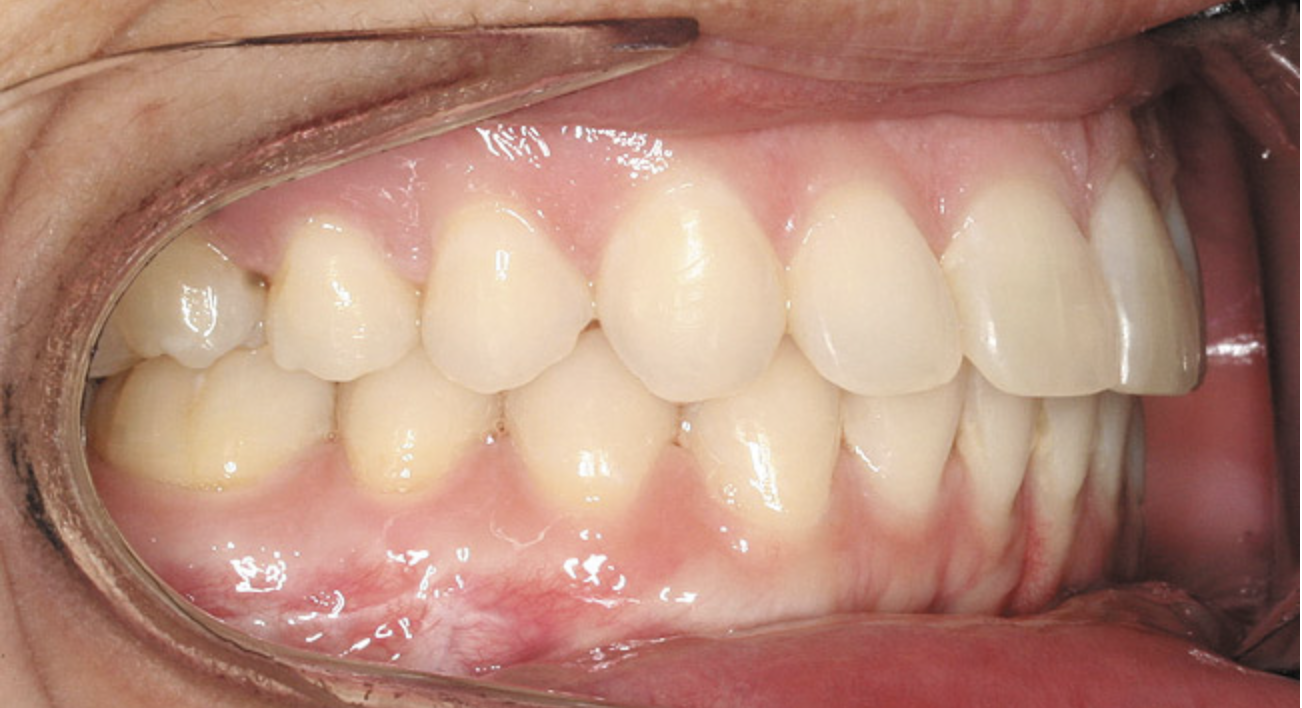

Figure 8  Intraoral view of the occlusion of patient from Figure 7 after retreatment. The occlusion is adequate to finish with equilibration.

Figure 8